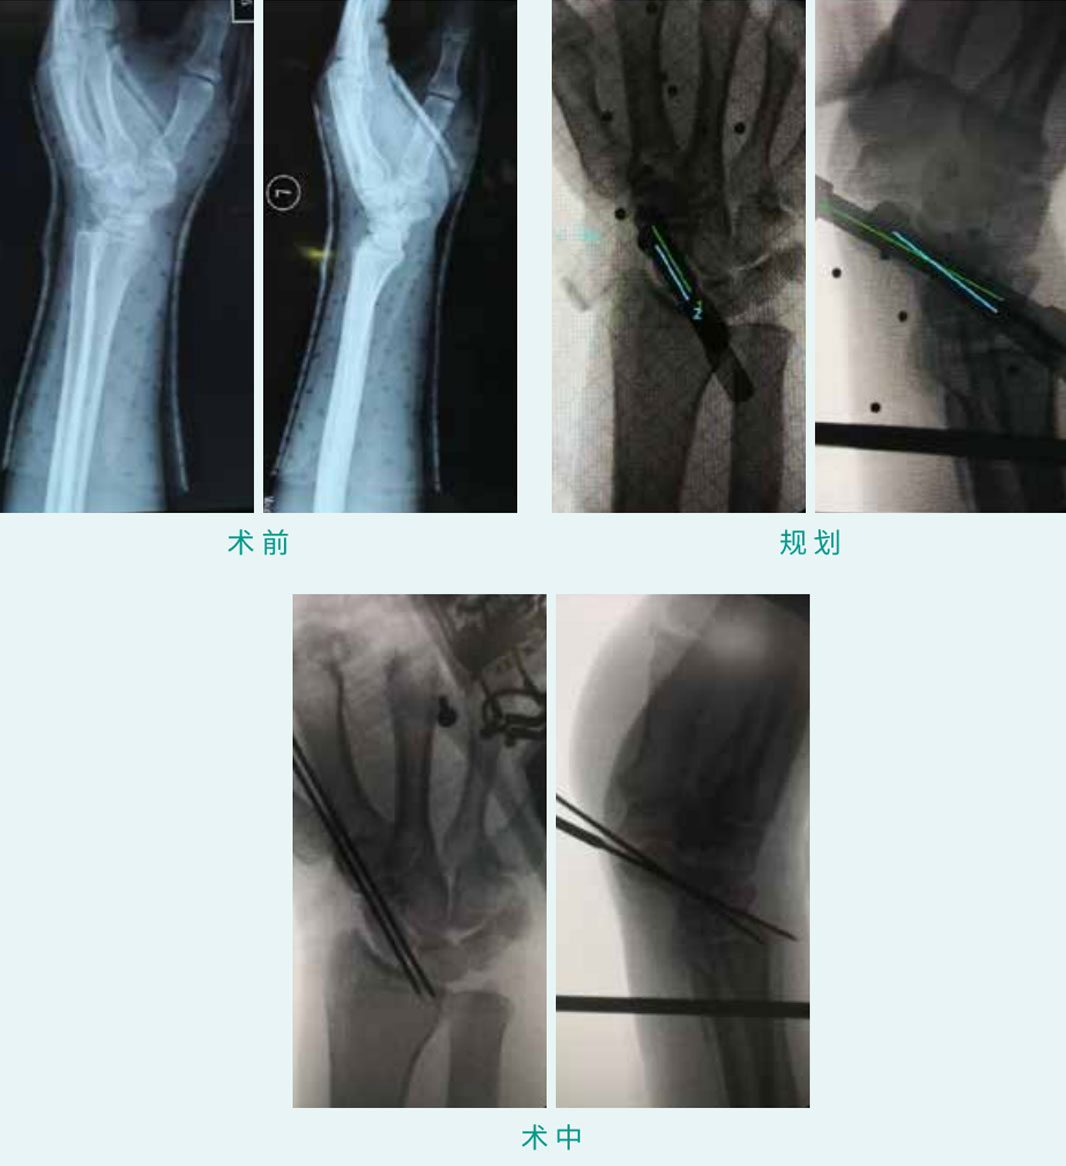

TiRobot ? Scaphoid Fracture Percutaneous Screw Fixation

天玑? 辅助手舟骨骨折经皮空心螺钉内牢靠术

基本情形:患者男,,,,,,30岁,,,,,,手舟骨骨折

机械人累积用时:20分钟

植入物:2枚空心螺钉

病例泉源:北京积水潭医院 郭阳